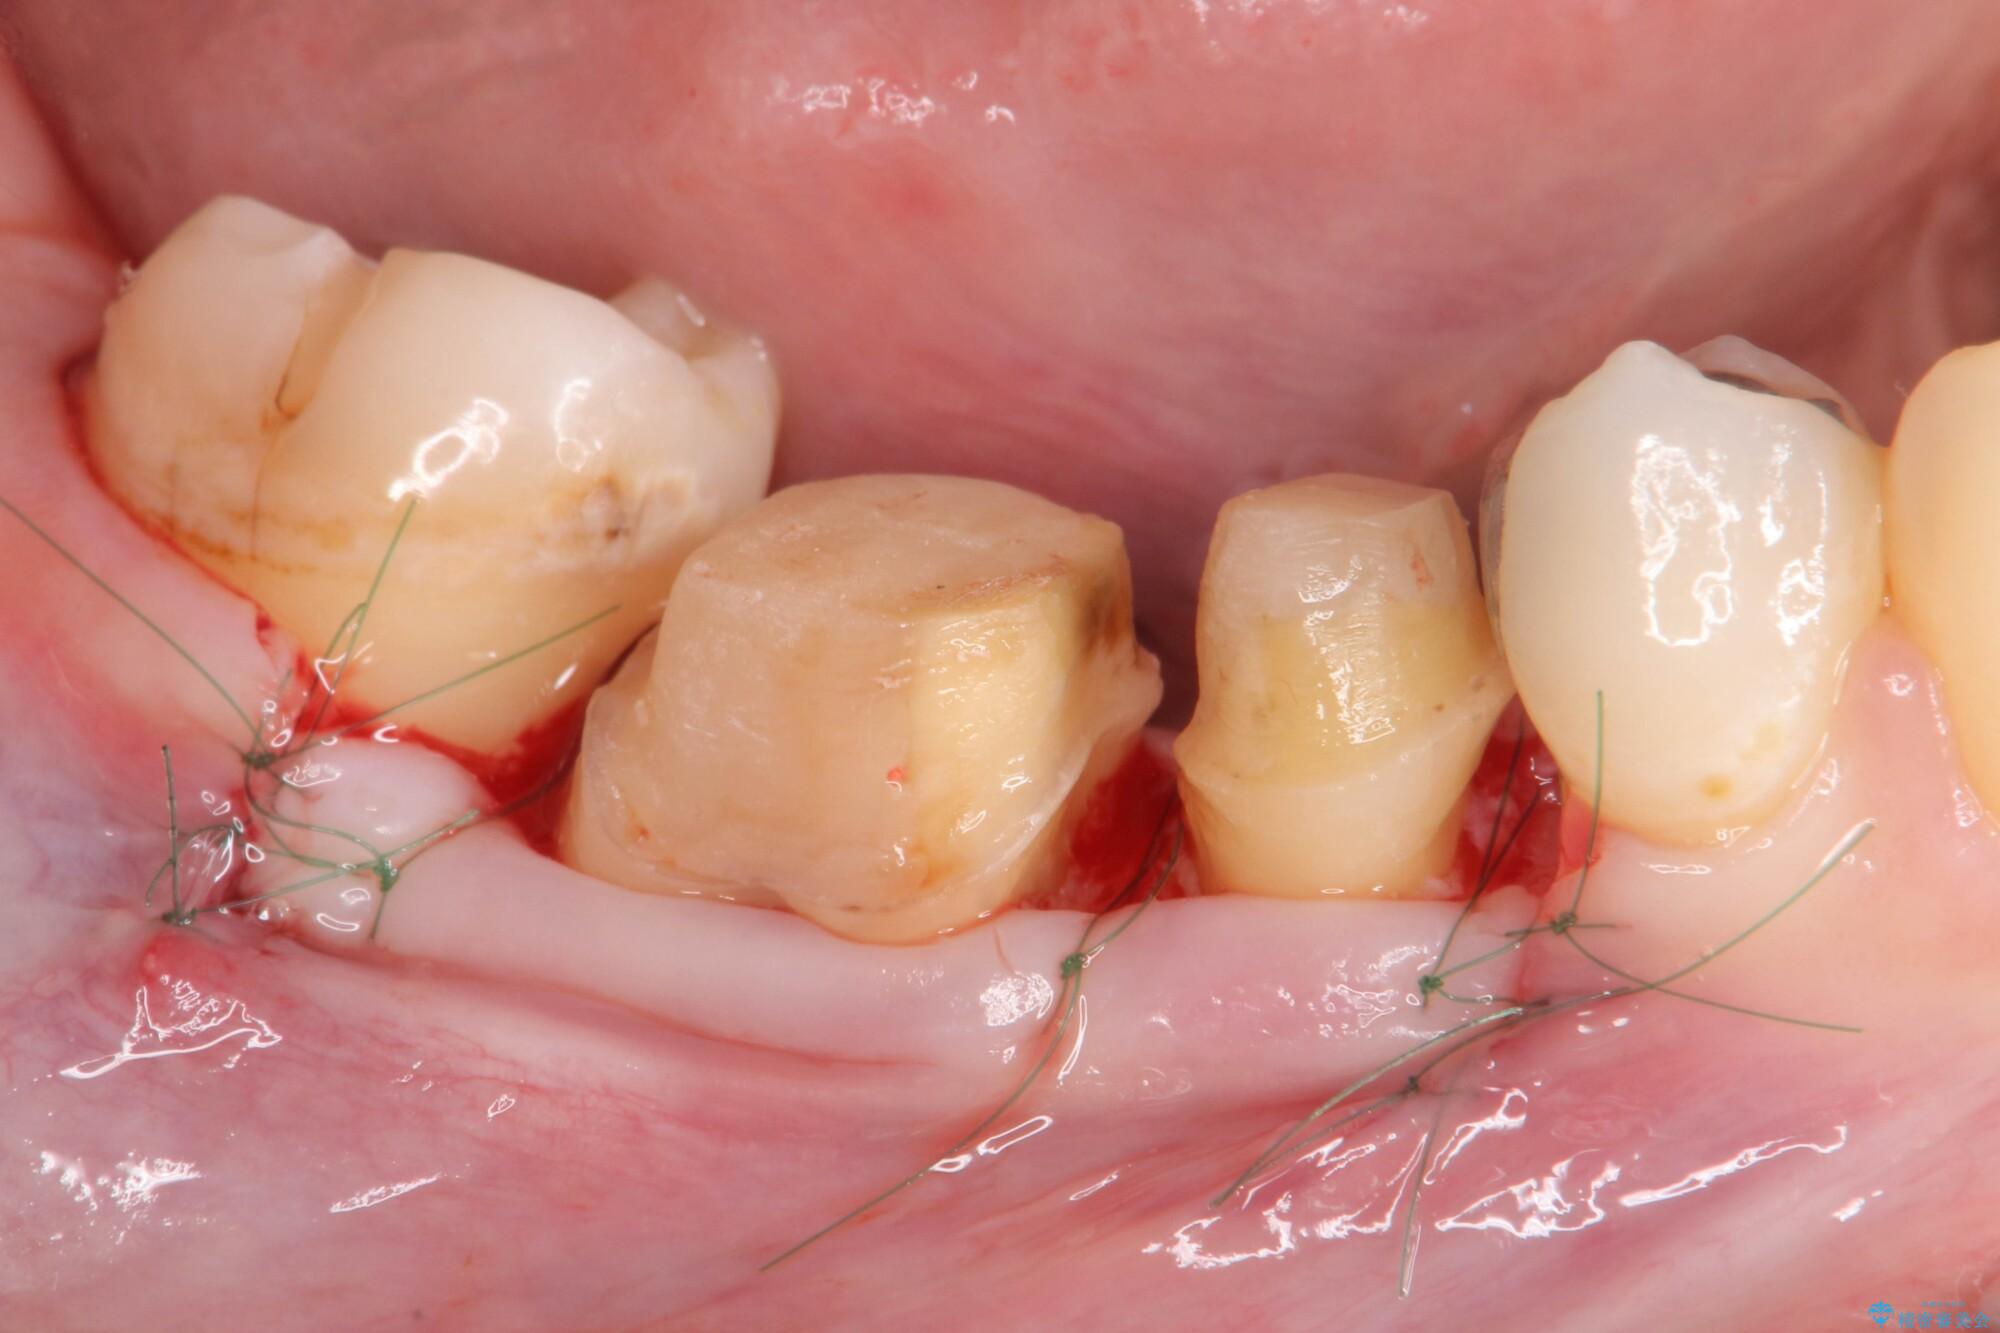

装着されていた清掃性の悪い銀歯を外すと、銀歯の下で歯ぐきよりも深い虫歯が再発していました。

虫歯を丁寧に除去し、歯周外科を用いて周囲の歯ぐきの炎症を除去します。その後、清掃性の高い精密なセラミック治療をおこなっていきます。